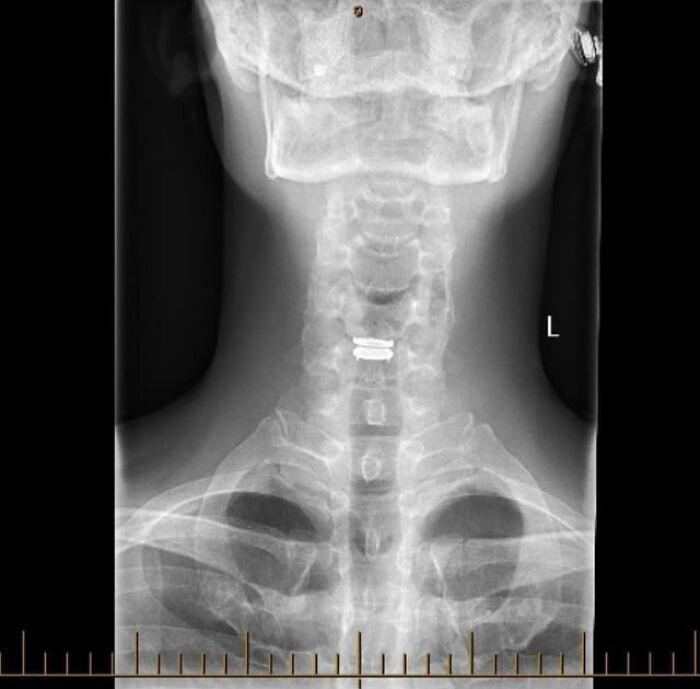

Check Out My New Neck Disc! Just Thought You’d Like to See It